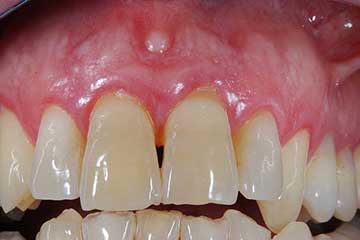

Con protesi fissa superiore e protesi fissa inferiore

I denti irrecuperabili dell'arcata superiore ed inferiore del paziente di anni 65

sono stati sostituiti da 10 impianti, cioè protesi radicolari endo-ossee che sostengono le protesi fisse superiore ed inferiore.